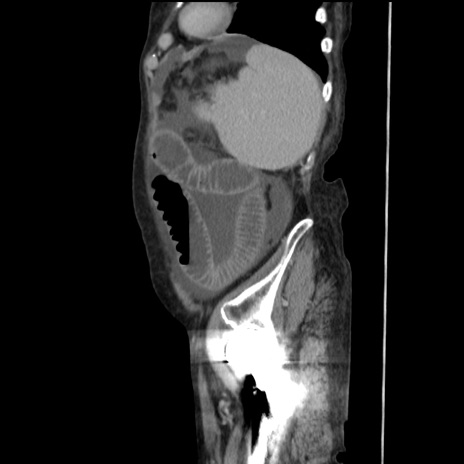

症例31(矢状断像)

【症例】80歳代 女性

【主訴】腹部膨満感

【現病歴】他院にて肝硬変にてフォロー中。1週間前から便秘、腹部膨満感、臍部腫瘤あり受診となる。

【既往歴】肝硬変

【身体所見】腹部膨隆あり、皮膚変化なし、疼痛なし。

【データ】WBC 4600、CRP 0.25